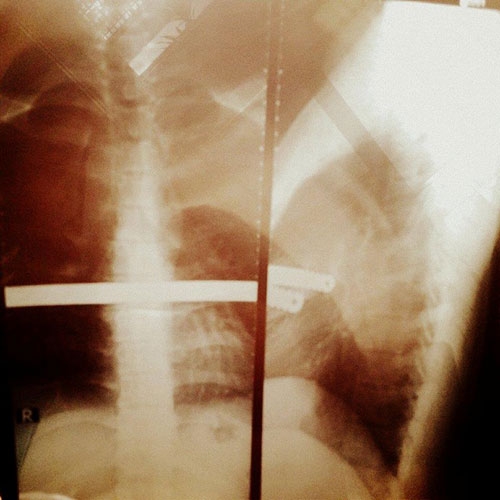

Dù rất đau lòng nhưng để giữ mạng sống cho con trai, gia đình anh chấp nhận phẫu thuật, chèn thanh sắt dài 30,5 cm trong lồng ngực Khánh. Suốt 3 năm qua, dù chung sống với "vật thể lạ" trong người nhưng 9X luôn động viên mình vượt qua.

| Thanh sắt dài 30,5 cm trong lồng ngực Khánh suốt 3 năm qua. |

Duy Khánh cho biết thanh sắt này chèn vào lồng ngực có tác dụng định vị xương tim và duy trì sự sống cho trái tim bệnh nhân. Hạn sử dụng tối đa của thanh kim loại này là hai năm, nhưng vì mải mê tham gia các hoạt động nghệ thuật nên Khánh đã trễ hẹn với bác sĩ một năm. Thời gian gần đây, những cơn đau lại xuất hiện.

Ngày 2/1, Khánh nhập viện để lấy thanh kim loại ra khỏi lồng ngực.